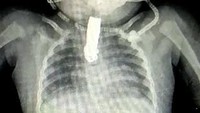

Pemeriksaan sinar-X menunjukan gunting kuku sepanjang 5 cm itu tersangkut dan menutupi hampir seluruh tenggorokan. (Foto: Newslion/SWNS)